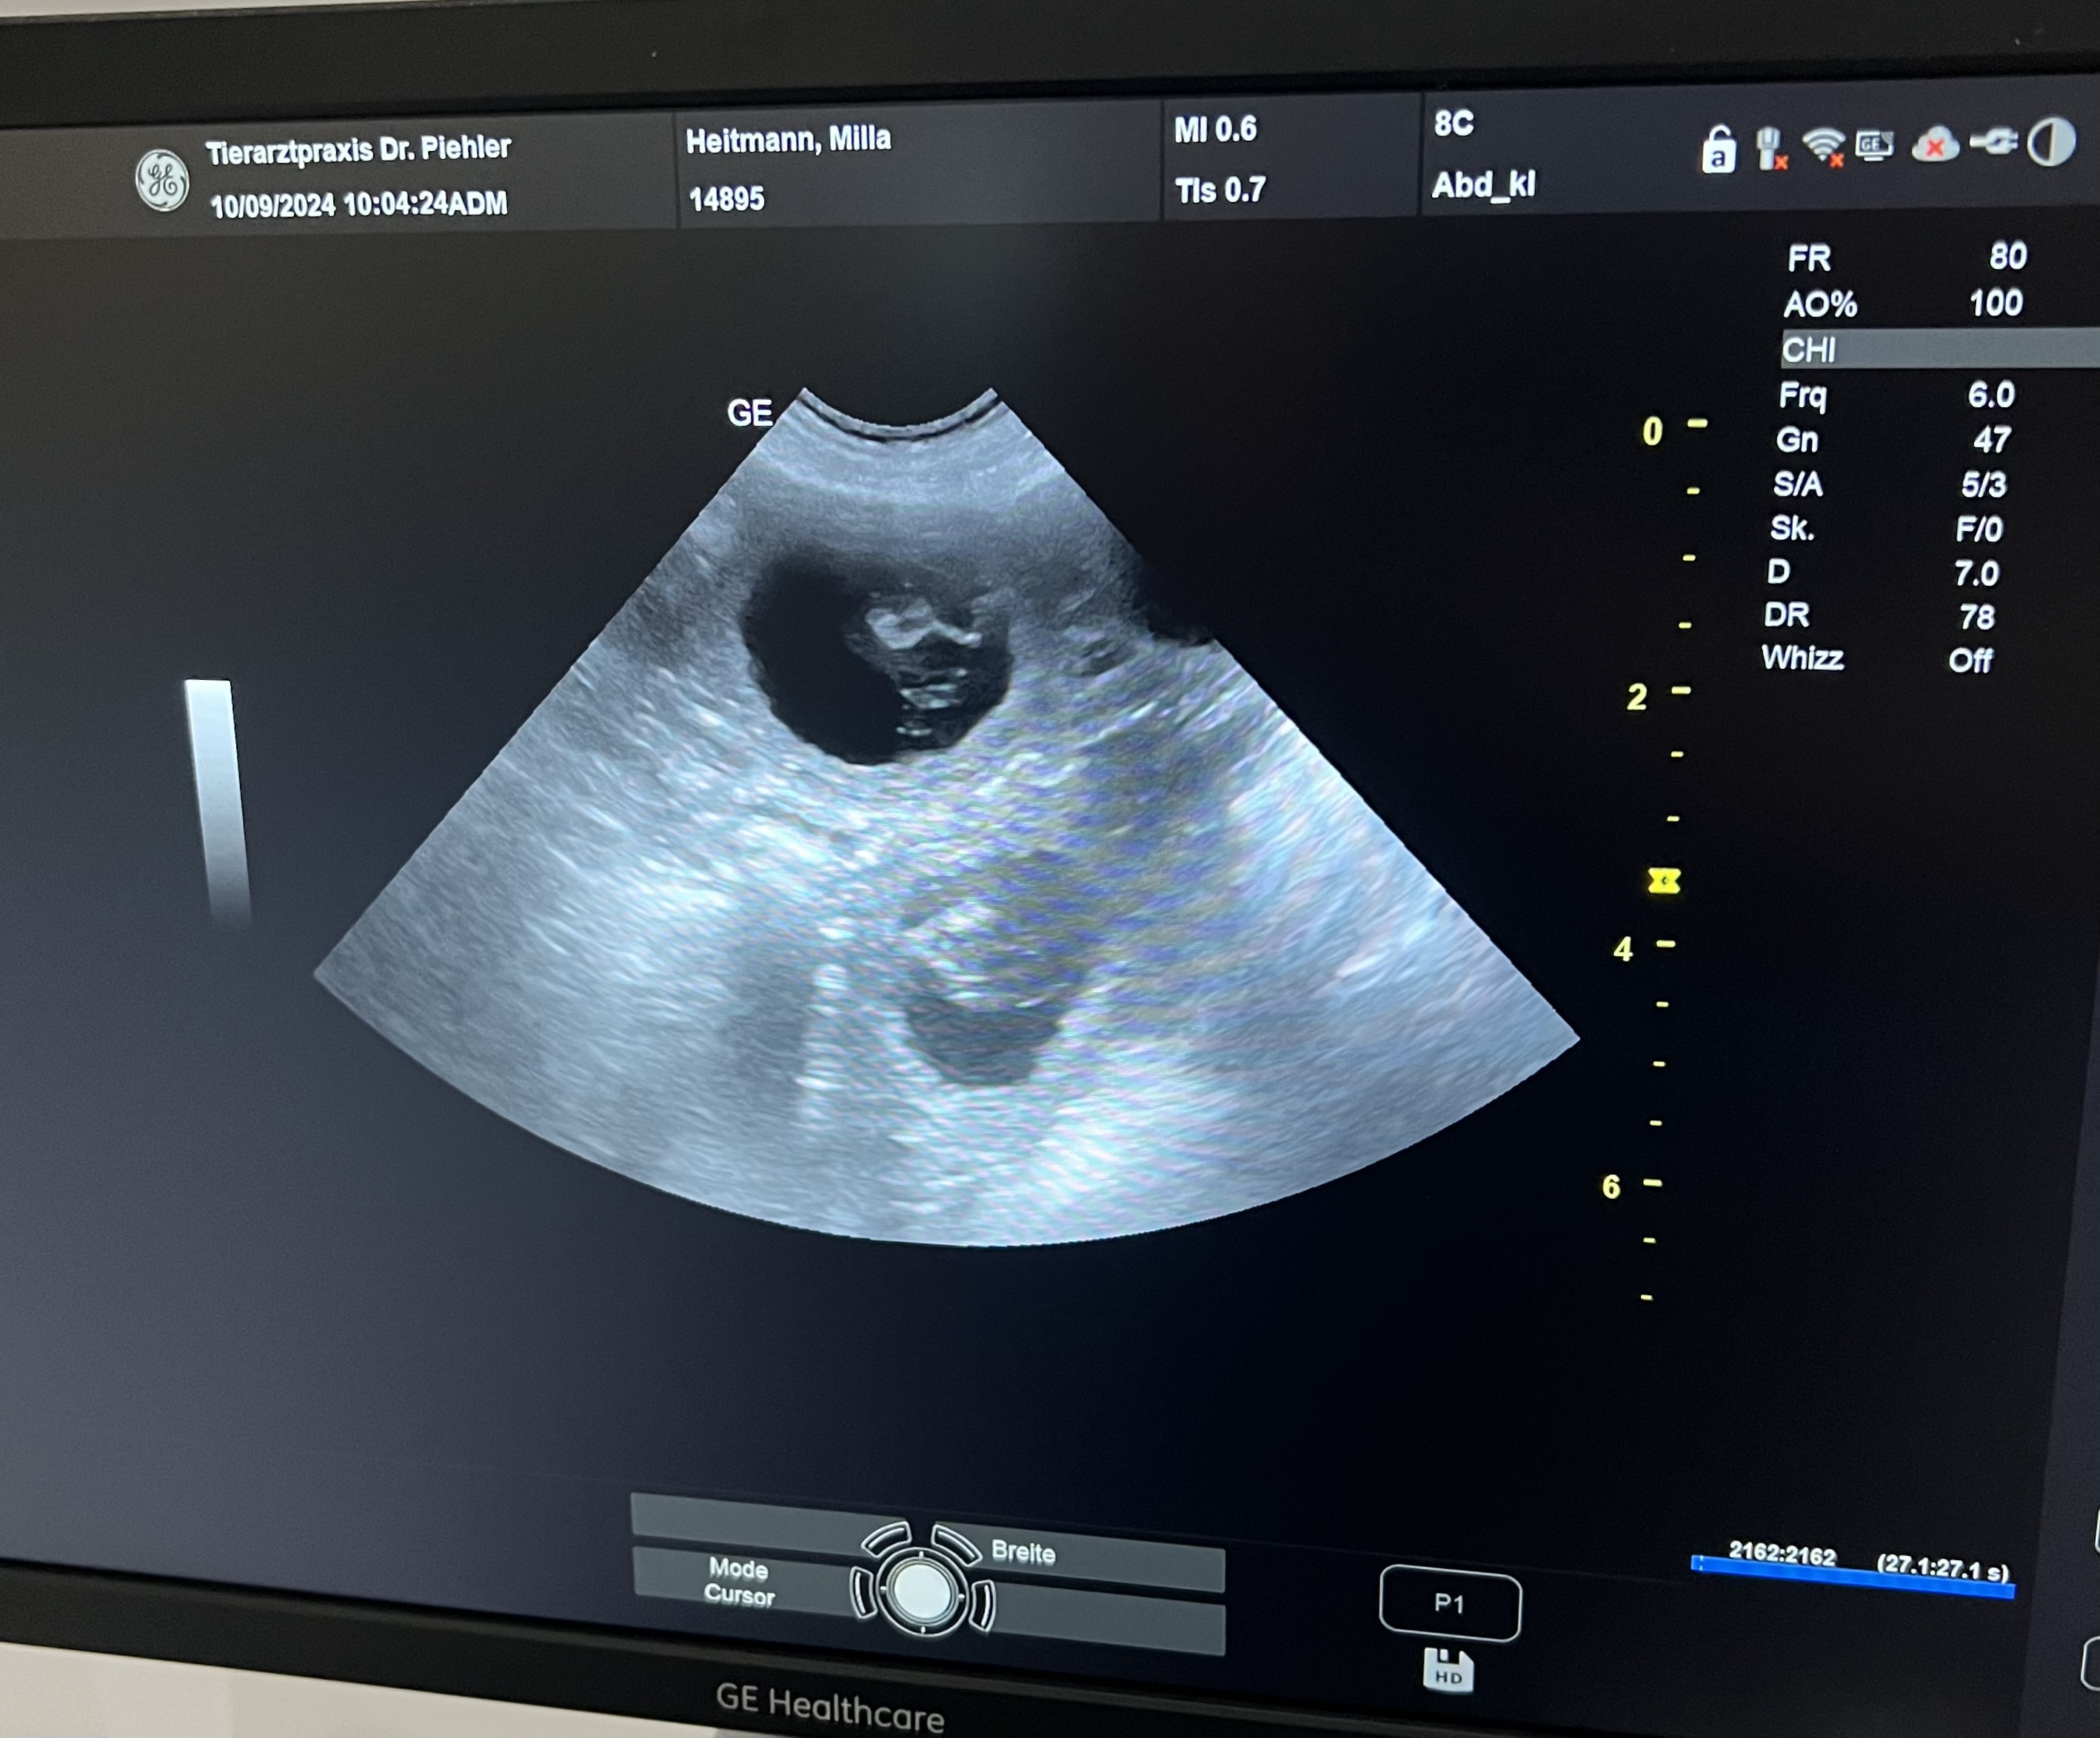

Am 11.10.2024 hat Milla 10 wunderschönen Welpen das Leben geschenkt.

Es sind 4 Rüden und 6 Hündinnen.

Die Kleinen können dann ab dem 06.12. in ihre neuen Familien ziehen.